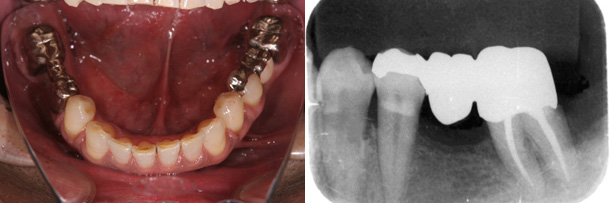

症例:下顎の前歯の叢生のみを改善

主訴:下の前歯のガタガタを治したい

診断:下顎前歯の叢生

年齢:62歳

装置:下顎部分的ブラケット装置

治療期間:6か月

抜歯:下顎前歯の1本

費用:100,000円+税

矯正前

矯正後